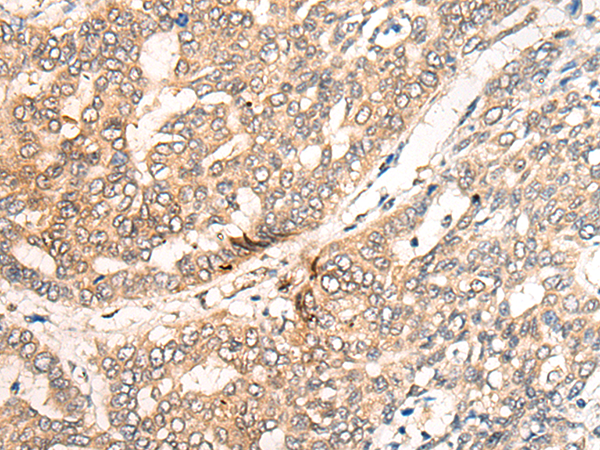

分类: 科研抗体货号: P09491别名: CFP1; CGBP; SPP1; PCCX1; PHF18; hCGBP; ZCGPC1; HsT2645; 2410002I16Rik; 5830420C16Rik应用: IHC反应种属: Human, Mouse